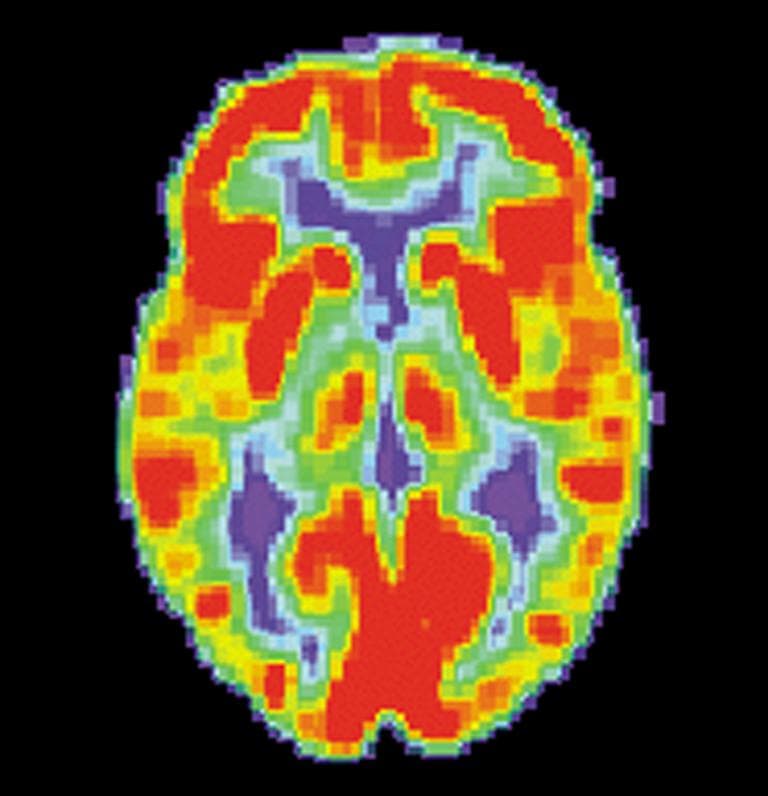

The new study, led by Dr. Helen Mayberg at Emory University in Atlanta, looked at PET scans from 63 depressed, untreated patients, and then divided them randomly into two groups, with half receiving cognitive behavioral therapy and half the anti-depressant escitalopram (brand name Lexapro) for 12 weeks. Activity in the insula, which is involved in emotional states and perceiving bodily sensations, predicted which treatment they would fare better on, the study showed.

Mayberg’s team hoped to identify a biomarker that could predict which type of treatment a patient would benefit from based on the state of his or her brain. Using a positron emission tomography (PET) scanner, they imaged pre-treatment resting brain activity in 63 depressed patients. PET pinpoints what parts of the brain are active at any given moment by tracing the destinations of a radioactively-tagged form of glucose, the sugar that fuels its metabolism.

They compared brain circuit activity of patients who achieved remission following treatment with those who did not improve.Activity in one specific brain area emerged as a pivotal predictor of outcomes from two standard forms of depression treatment: cognitive behavior therapy (CBT) or escitalopram, a serotonin specific reuptake inhibitor (SSRI) antidepressant. If a patient’s pre-treatment resting brain activity was low in the front part of an area called the insula, on the right side of the brain, it signaled a significantly higher likelihood of remission with CBT and a poor response to escitalopram. Conversely, hyperactivity in the insula predicted remission with escitalopram and a poor response to CBT.

Among several sites of brain activity related to outcome, activity in the anterior insula best predicted response and non-response to both treatments. The anterior insula is known to be important in regulating emotional states, self-awareness, decision-making and other thinking tasks. Changes in insula activity have been observed in studies of various depression treatments, including medication, mindfulness training, vagal nerve stimulation and deep brain stimulation.